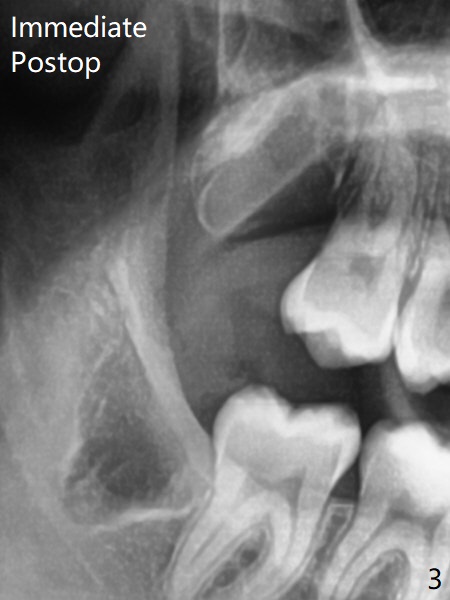

Xin Wei, DDS, PhD, MS 1st edition 11/21/2020, last revision 11/23/2020